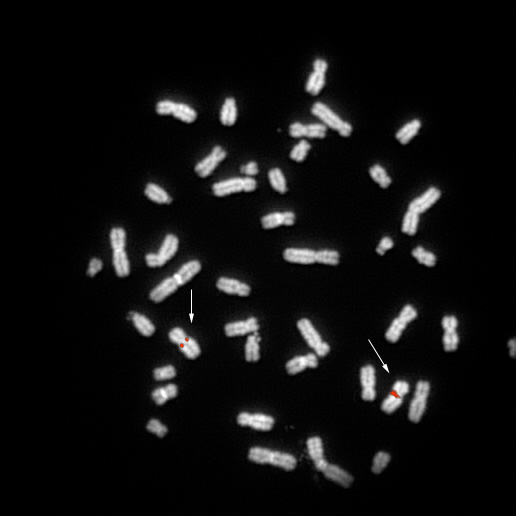

RP5-376D21